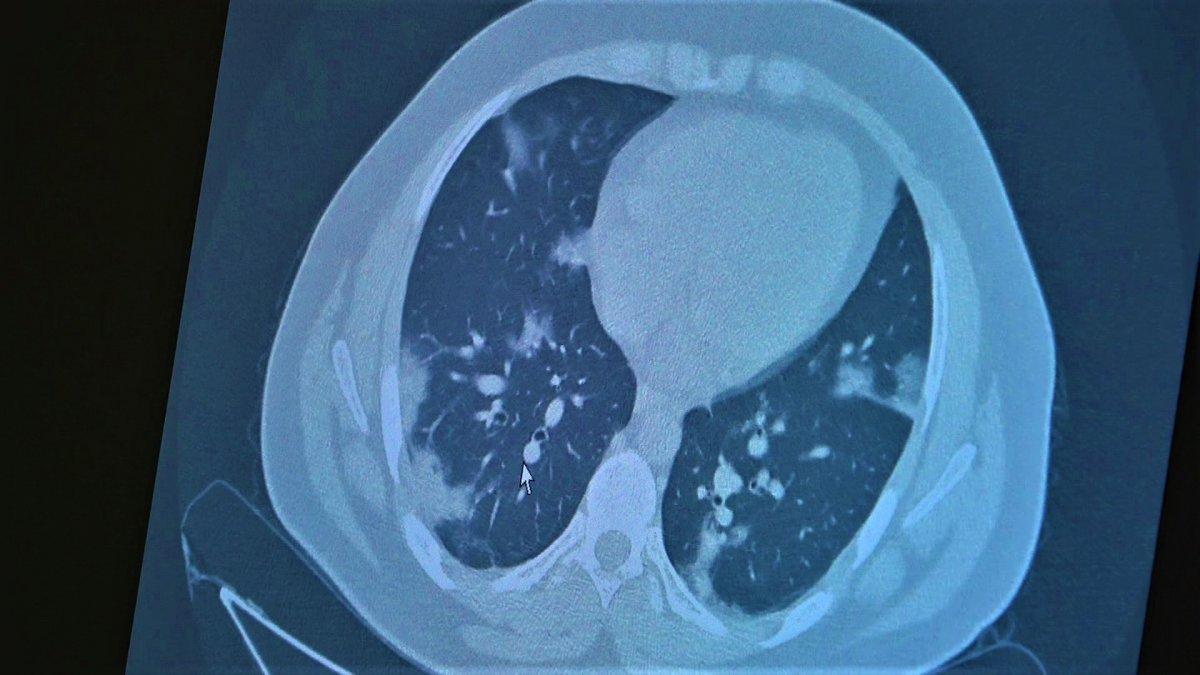

Çocukların akciğer tomografilerini inceleyen Özkaya, açıklamalarına şu ifadeler ile devam etti:

14 yaşında pozitif olan bir diğer çocuğumuz ise aşı randevusu almış ama aşısını olmadan ateş ve öksürükle başvurdu. Halen şanslıyız. Çocuklar çok hızlı tedaviye yanıt veriyor. Düzeldi. Çekilen tomografisinde ise bilaterel yaygın tutulumları vardı. Bu ise 24 yaşında genç hastanın akciğer tomografisi. Bu kişide yaygın akciğer tutulumları görüldü. Bunu da tedavi ettik. Önümüzdeki aylarda ne getirecek ne götürecek beraber göreceğiz. Özellikle havaların soğumasıyla kapalı ortamlarda geçilen zamanın ve kalabalıkların etkisiyle vaka sayılarının önümüzdeki günlerde artacağını biliyoruz. Şu an gerçekten hastalık gençlerde 30 -40 yaş altı gençlerde görülmeye başladı. Poliklinik şartlarında olanların büyük bir kısmı 30 yaş altı hastalar. Servislerde yatanlarda orta yaş ve altı nüfus. Yoğun bakımda yatanların büyük bir kısmı ise aşısız erişkin insanlardan oluşuyor.”